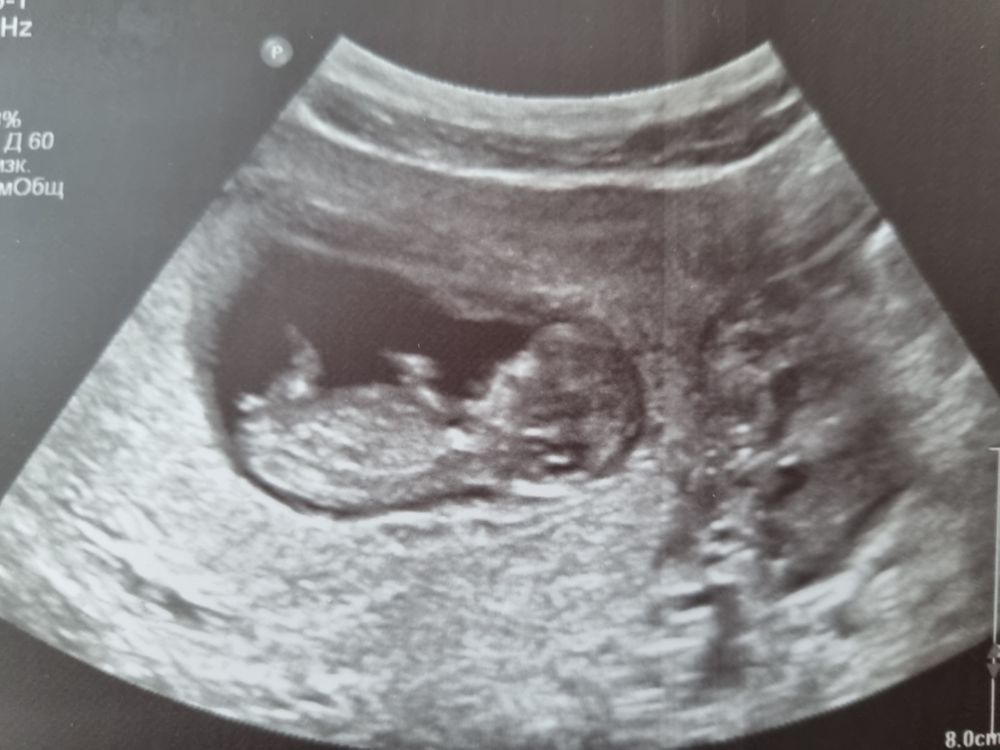

Фото

Анастасия ,